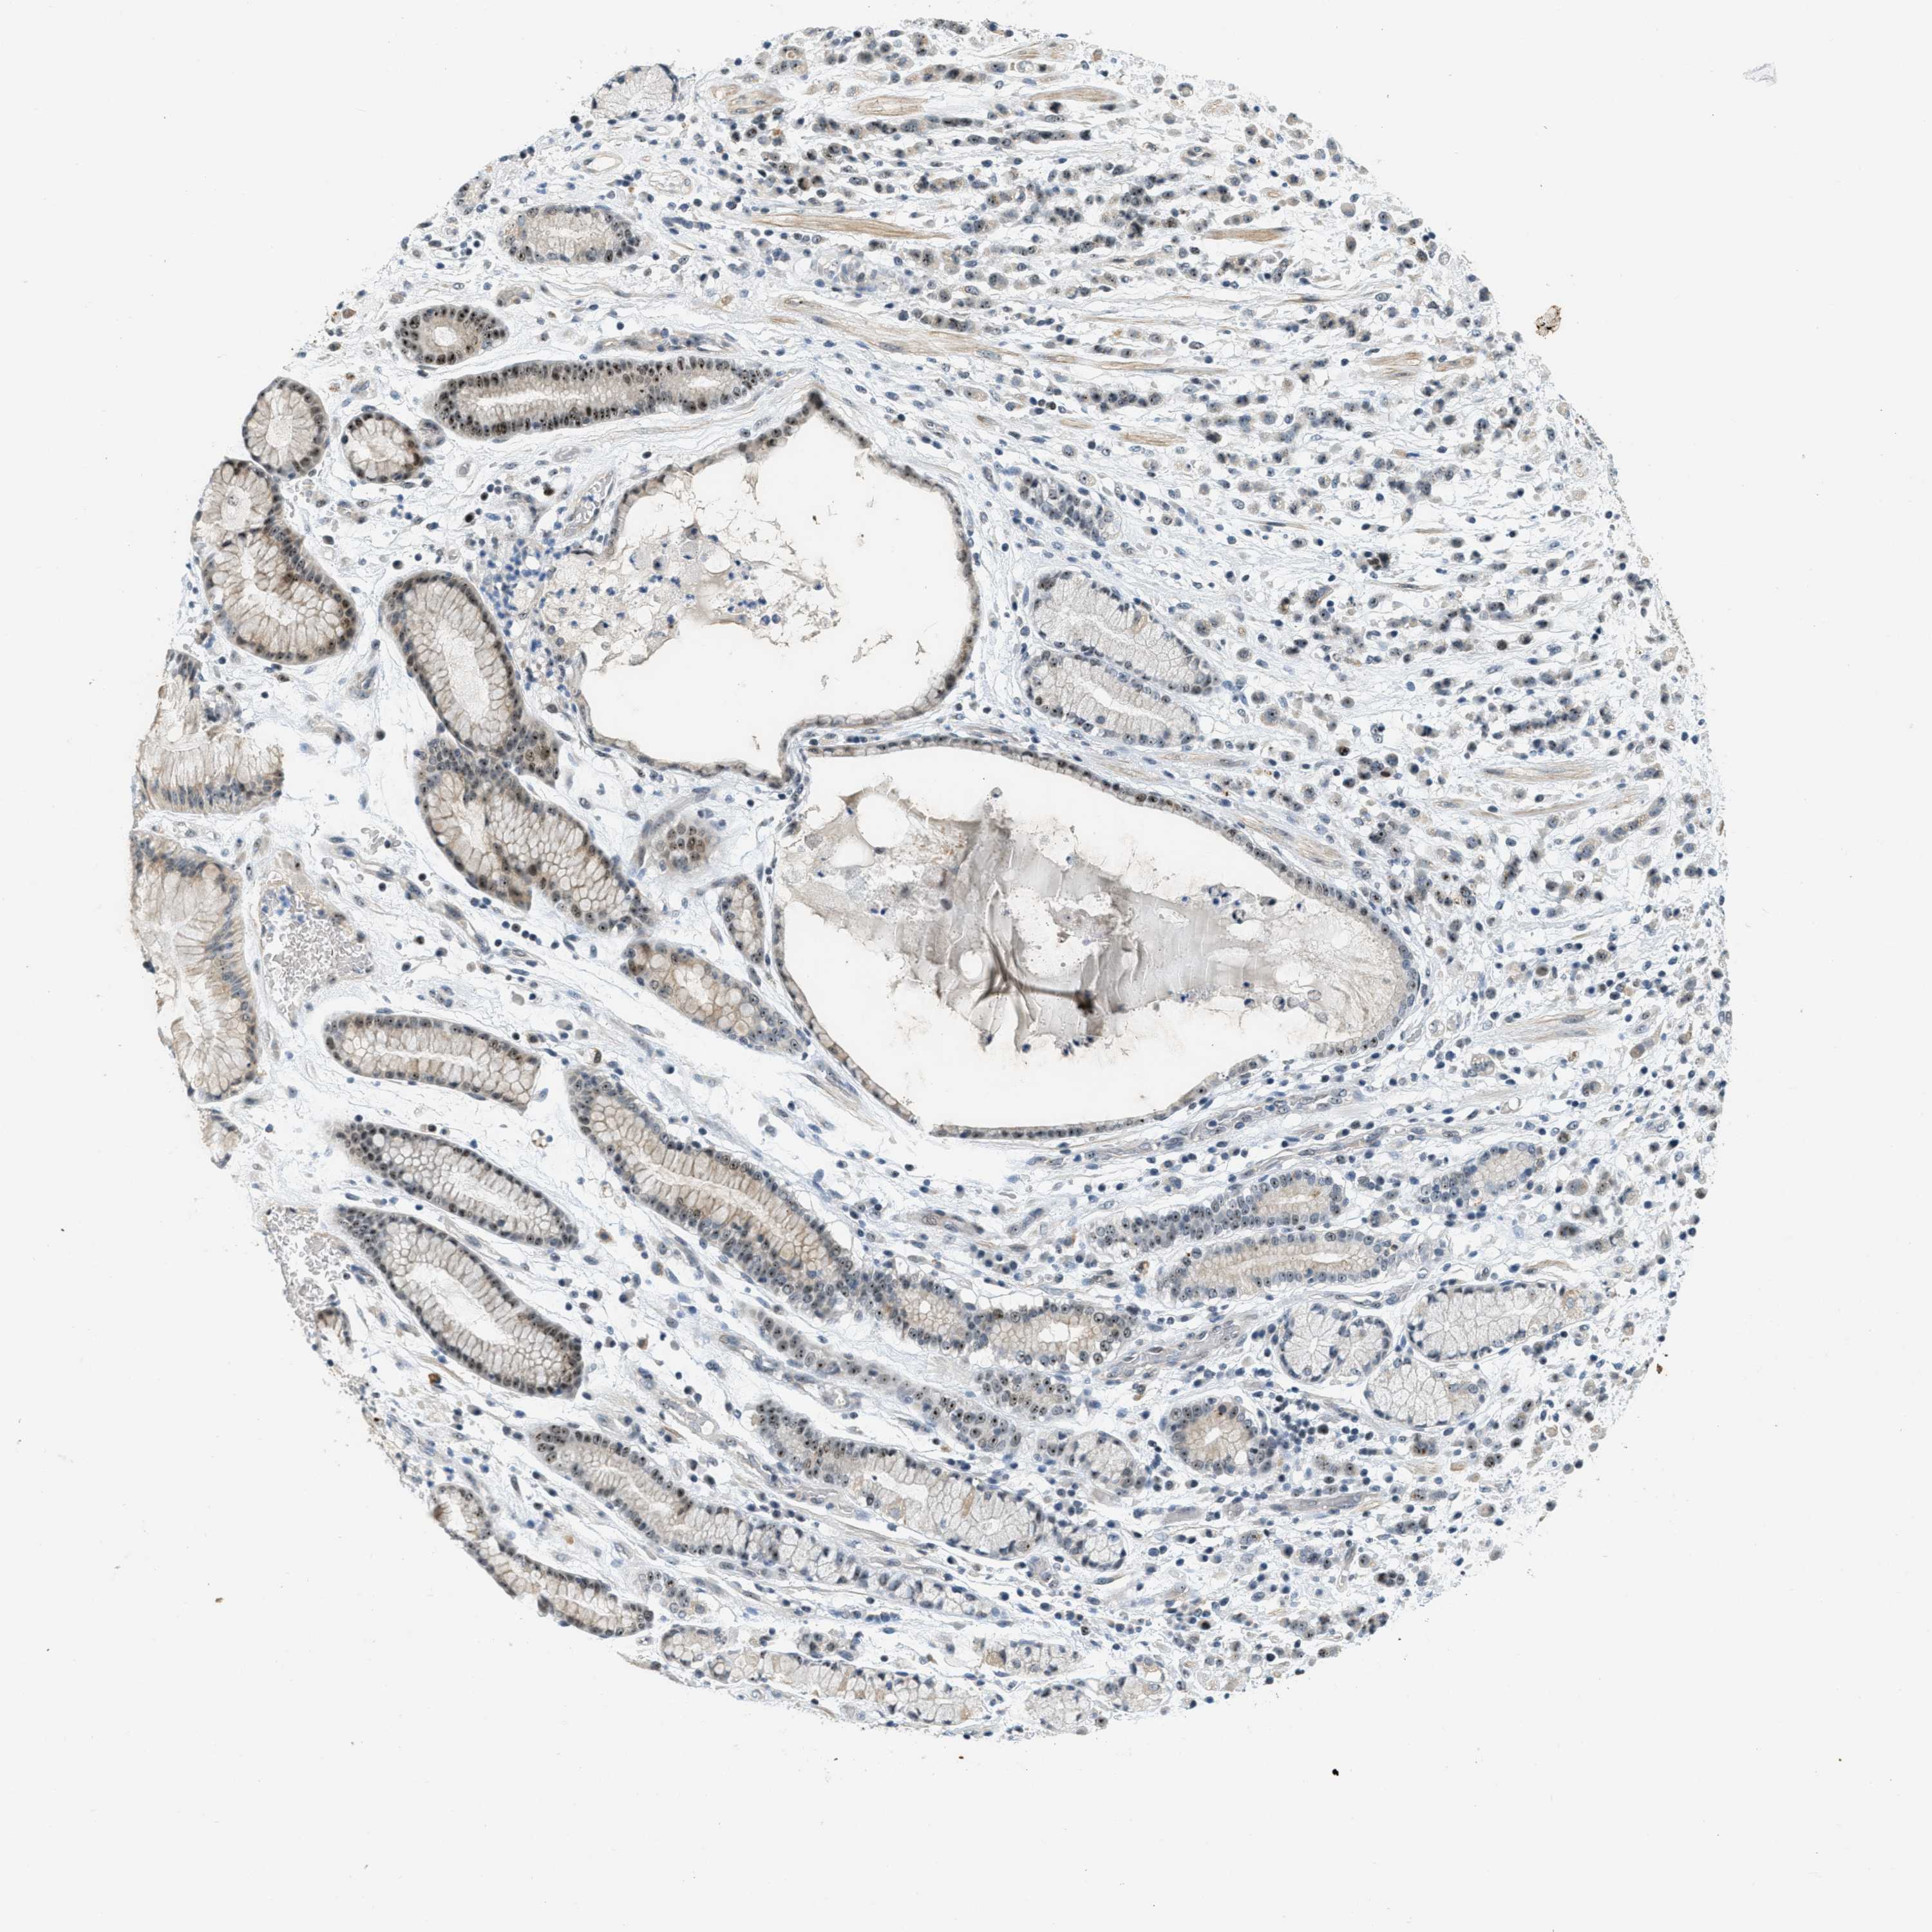

STOMACH CANCER - Protein expressioni

A mouse-over function shows sample information and annotation data. Click on an image to view it in a full screen mode. Samples can be filtered based on level of antibody staining by selecting one or several of the following categories: high, medium, low and not detected. The assay and annotation is described here.

Note that samples used for immunohistochemistry by the Human Protein Atlas do not correspond to samples in the TCGA dataset.

Antibody stainingi

Antibody staining in the annotated cell types in the current human tissue is reported as not detected, low, medium, or high, based on conventional immunohistochemistry profiling in selected tissues. This score is based on the combination of the staining intensity and fraction of stained cells.

Each image is clickable and will lead to virtual microscopy that enables deeper exploration of all samples and also displays staining intensity scores, fraction scores and subcellular localization as well as patient and tissue information for each sample.

Antibody HPA014855

Staining

High

Medium

Low

Not detected

Intensity

Strong

Moderate

Weak

Negative

Quantity

>75%

75%-25%

<25%

None

Location

Nuclear

Cytoplasmic/membranous

Cytoplasmic/membranous,nuclear

Adenocarcinoma, NOS